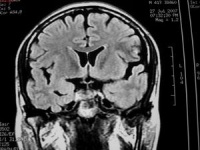

MRI表现

在脑部动静脉畸形的诊断上有较大优越性,尤其是后颅窝病灶,诊断价值大于CT。因此,当怀疑病人患有脑血管畸形时,MRI为首选的影像检查手段。①脑动静脉畸形的血管成分,表现为成团状、网状分布的无信号流空血管影。其中供血动脉,在T1和T2加权像上因流空现象而表现为低信号或无信号影。引流静脉则因血流缓馒,T1加权像呈低信号,T2加权像为高信号像。血管的钙化表现为低信号或无信号暗区。动静脉畸形中的血栓,在T1和T2加权像均表现为低信号夹杂等信号或高信号和低信号内夹杂高信号影。②动静脉畸形出血形成血肿,则表现为T1和T2加权像变化和其他原因所致血肿相似。亚急性期血肿,在T1和T2加权像上均为高信号,随时间延长,血肿在T1加权像上信号逐渐变为等信号或低信号,T2加权像上仍为高信号。